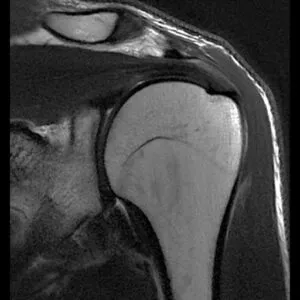

MRI

GE社製のSIGNA Creator 1.5T(テスラ)を導入しています。強力磁石と電波を使って体内の状態を鮮明に見ることができます。膝関節疾患を始めとする他の関節の疾患はもちろん、神経、筋肉・腱の異常や、腫瘍病変などの診断に有用です。

MRIで検査した画像